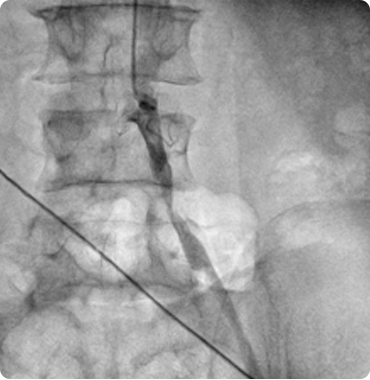

Interesting Cases